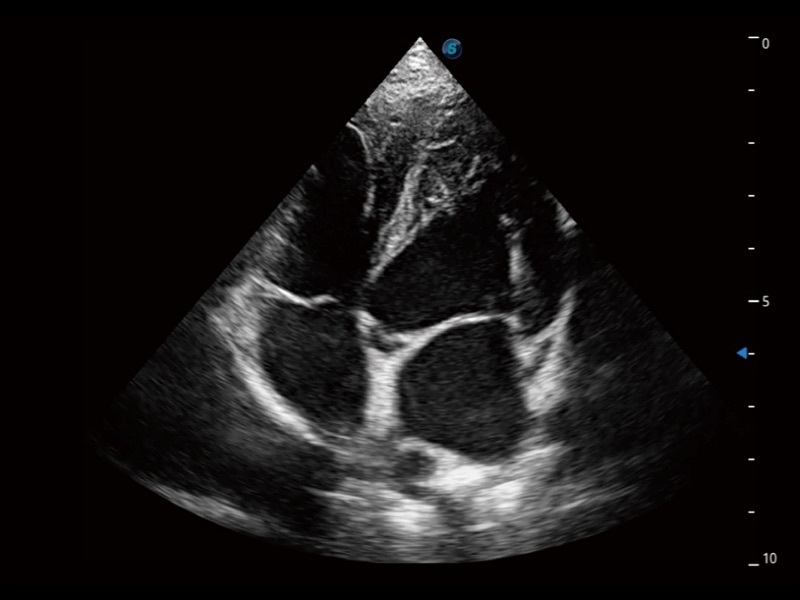

优异的基础图像

(犬)四腔心